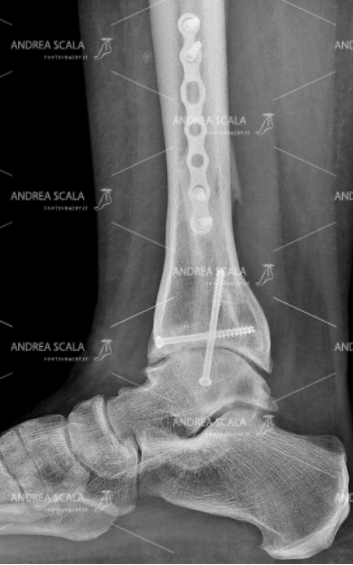

La RXgrafia anteriore della caviglia mostra che a distanza di 5 anni lo spazio articolare è molto ridotto e le ossa della caviglia si toccano.

La RXgrafia laterale della caviglia mostra che è diminuito lo spazio articolare ed il contatto tra le ossa. L’attrito causa un forte dolore, gonfiore e limitazione della articolazione.